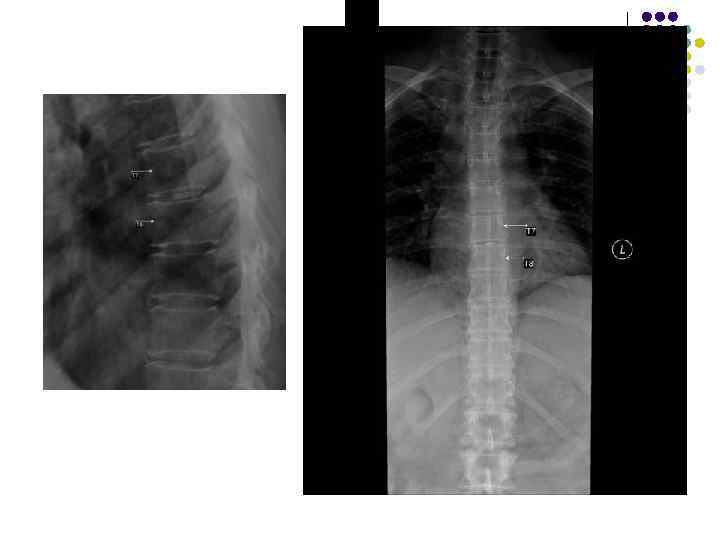

Обызвествления межпозвоночного диска • Чаще локальное обызвествление желатинозного ядра или отдельных участков фиброзного кольца • Редко обызвествляется весь диск • Часто сочетается с умеренным остеохондрозом передних участков диска • Как правило, не вызывает никаких субъективных и объективных симптомов, являясь случайной находкой

Обызвествление дисков

Обызвествление дисков l МРТ

Обызвествление межпозвоночного диска